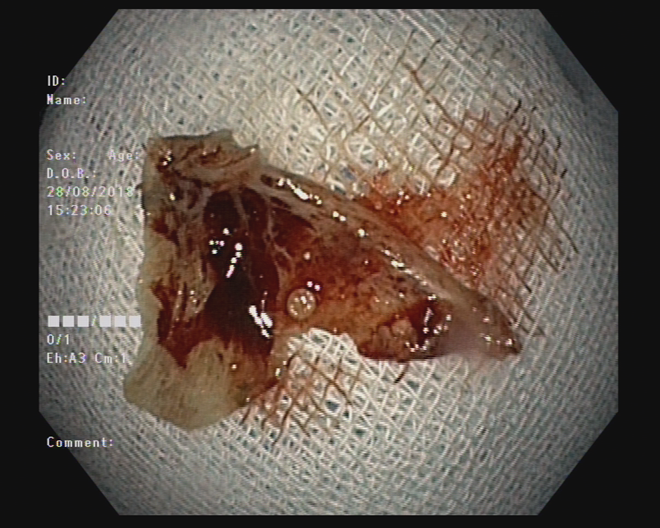

Mảnh xương cá đã được gắp ra ngoài qua nội soi.